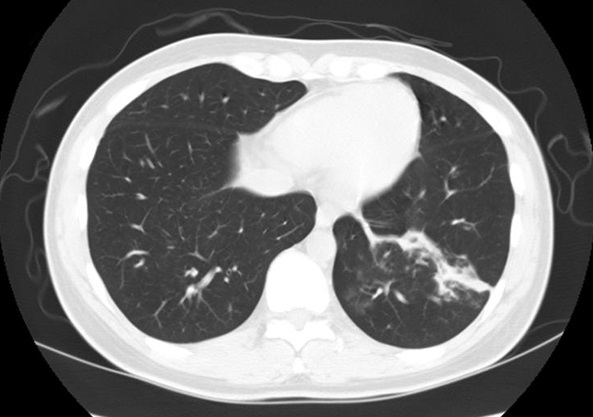

F/27

C.C : 2°³¿ù ÀüºÎÅÍ ¹Ýº¹µÇ´Â cough, sputum, rhinorrhea.

P/Ex. : wheezing on both lower lung fields.

Chest PA, Chest CT, Bronchoscopy , M-test was done.

Methacholine bronchial challenge test (+)